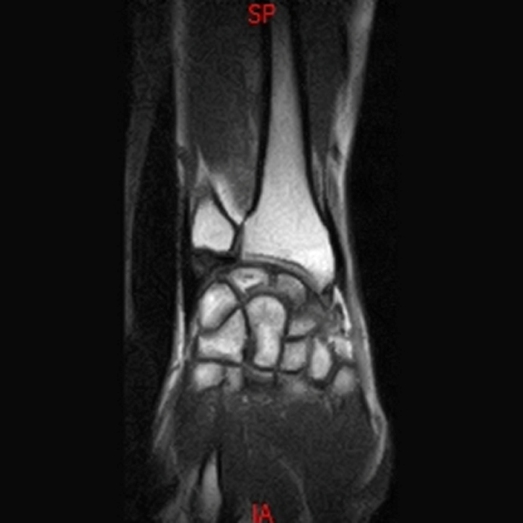

• RESONANCIA NORMAL TOBILLO SAGITAL T1